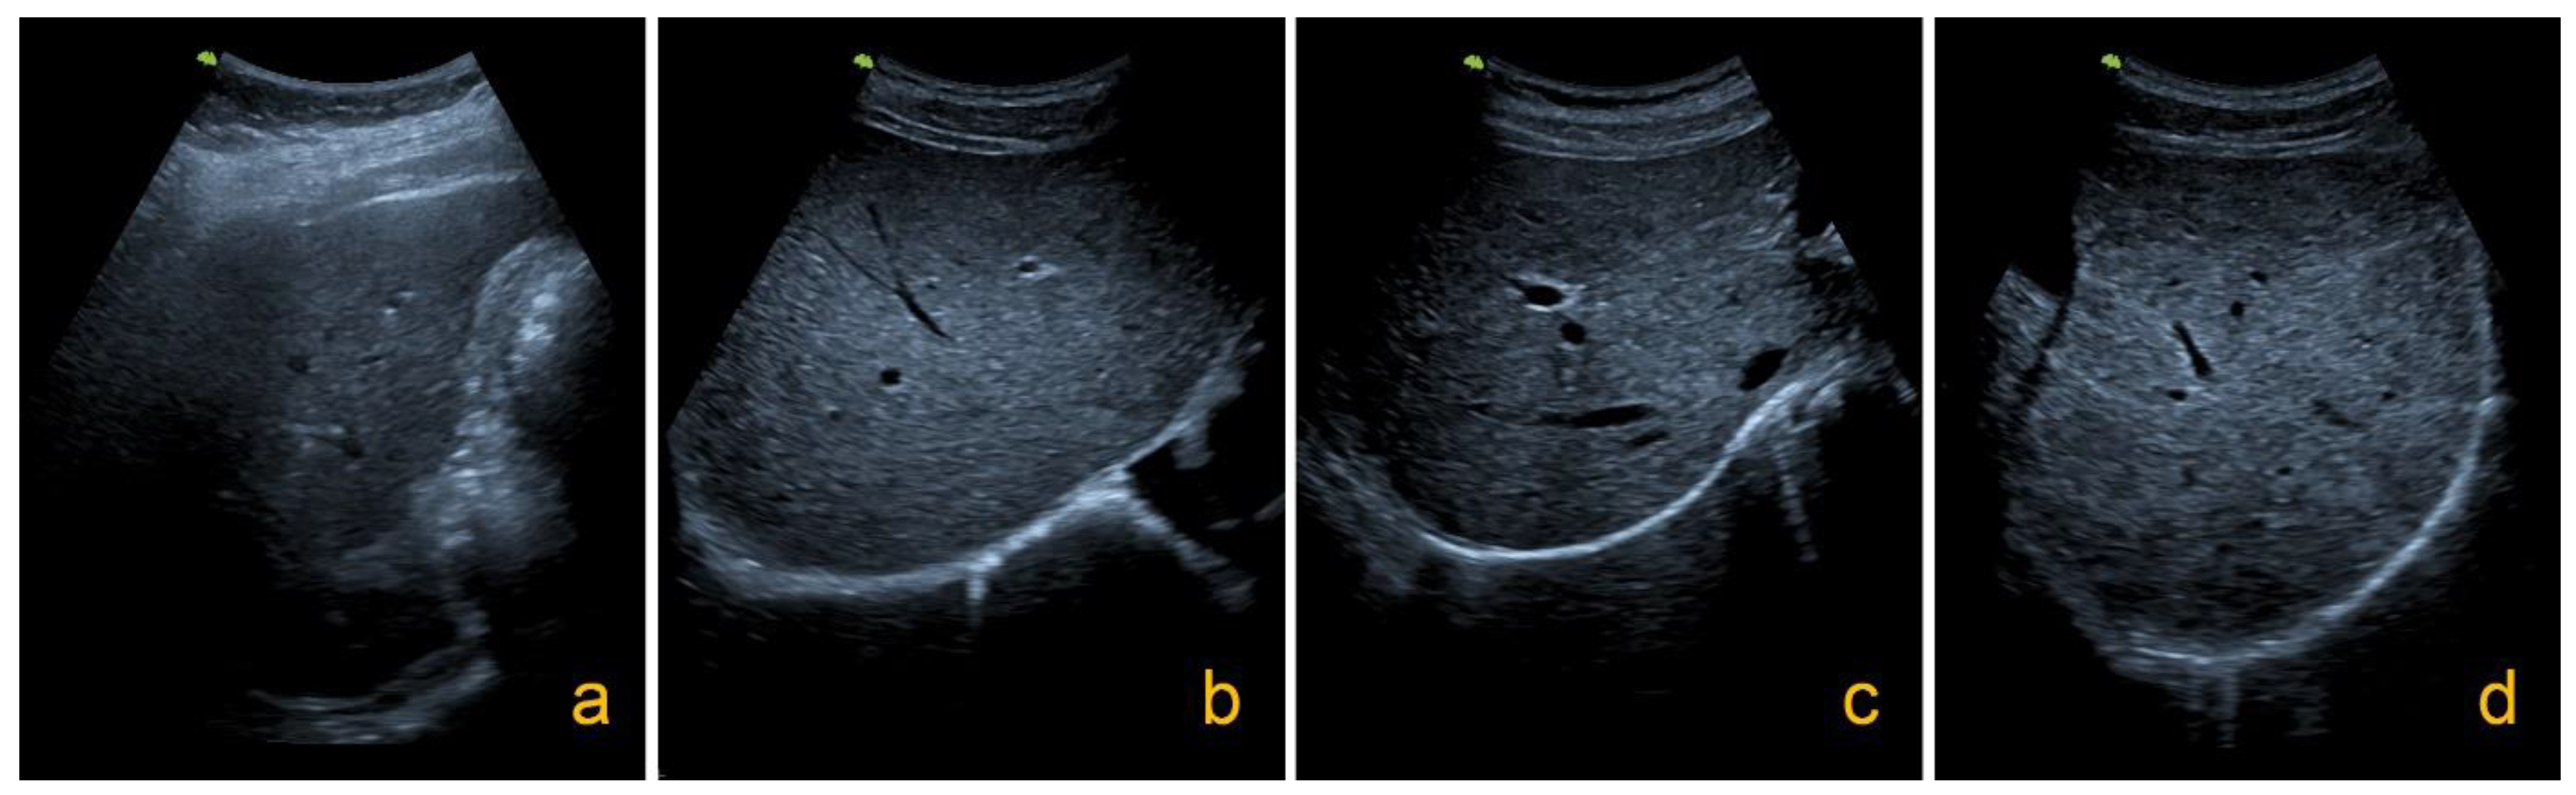

4.3. Ultrasound Examination